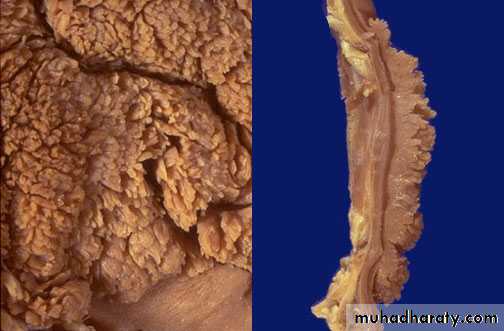

Morhophology: Adenocrcinoma

Intestinal Type :

Grossly : Exophytic , Nodular, ulcerative Excavaeted.

Microscopically: glandular component of malignant cells.

Diffuse type:

Infitrative to gastric wall , malignant cells had intracellular mucin push the nucleus to the periphery (Linitis Plastica)SMALL INTESTINE AND COLON